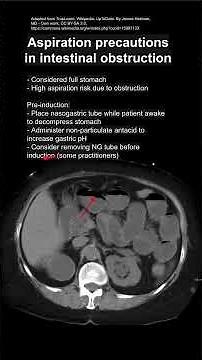

Aspiration precautions in intestinal obstruction

742 views

10 months ago

YouTube

MedLecturesMadeEasy